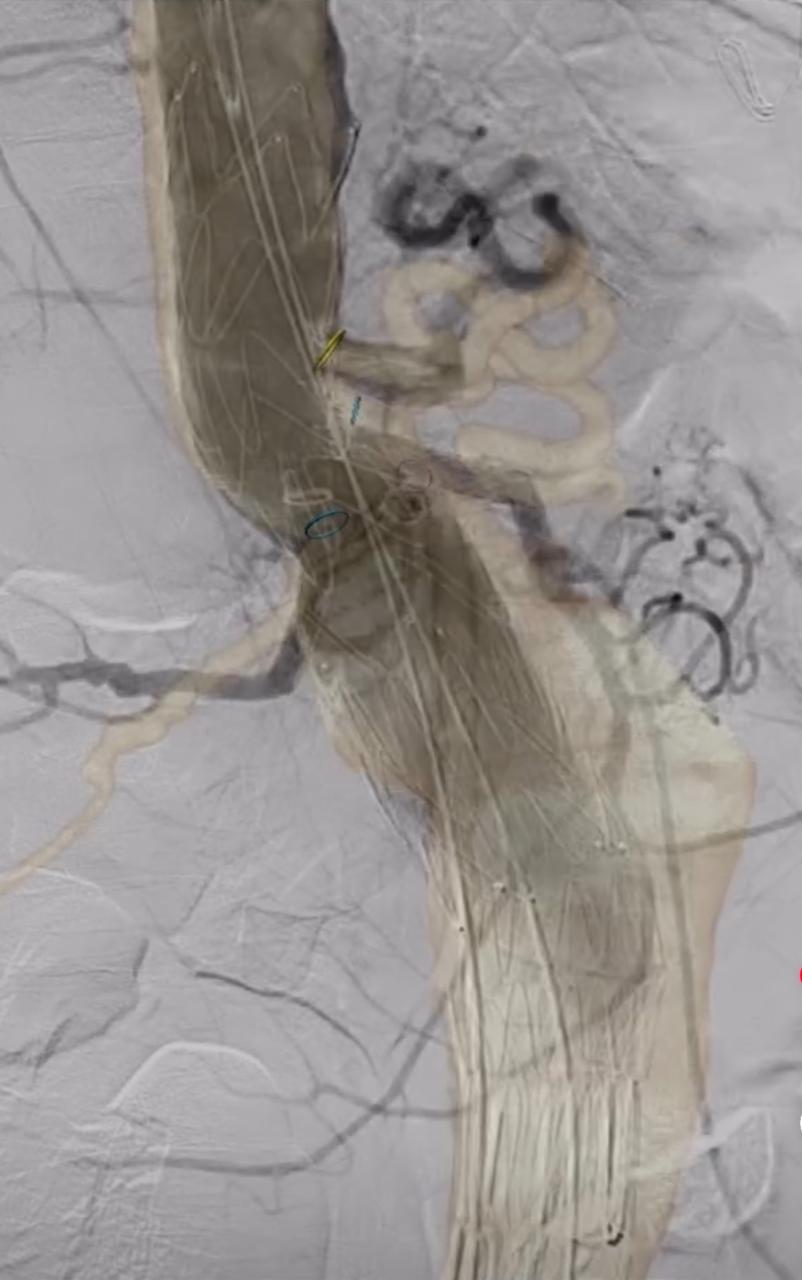

Tecnología de Punta

En las Clínicas Medellín de Occidente y Vegas se cuenta con tecnologia de punta en imágenes y terapia endovascular